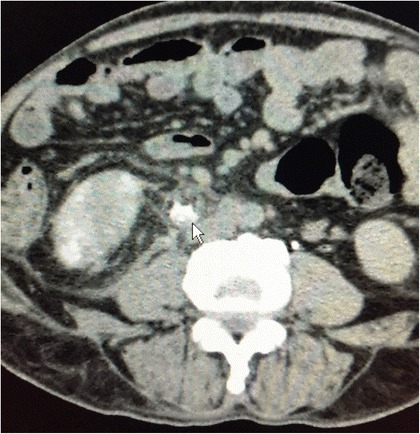

However, a CECT scan when done, reported a ureteric rupture with leakage of contrast from the upper ureter, well away from the renal pelvis, at the level of the 2nd lumbar vertebra (Fig. 1).

Fig. 1.

CECT with arrow demonstrating contrast leak from the upper ureter, well away from the fornix